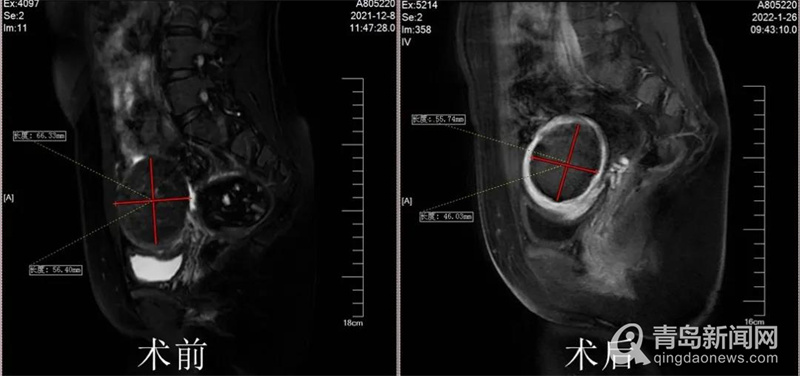

手术如期进行,经过一个半小时的海扶治疗,有效消融了Rose女士子宫侧壁最大的肌瘤和其他小肌瘤,同时内膜、浆膜没有一点损伤。看着自己的术后检查结果,Rose女士心里的石头终于落了地,24小时后恢复良好的她顺利出院。